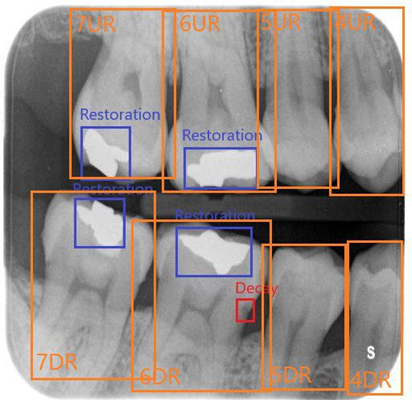

As the main product of Smartory startup, Smarteeth is a collaborative project with Shahid Beheshti Medical University, focused on developing an AI-powered assistant for diagnosing dental disorders using various radiography images (panoramic, bitewing, and periapical) and RGB images taken by mobile cameras. I was part of the core research and development team, where we collected and annotated over 100,000 radiography images and established a standard protocol for medical history and diagnosis forms in clinics. The AI tasks in this project include classification, detection, and segmentation of dental disorders, while Large Language Models (LLM) were used to generate basic diagnostic reports and basic suggestions based on the teeth condition. The project received significant attention at Exida, the International Congress of Dentistry, and has resulted in published research at the ICROM conference, with two more papers in progress. A free sample of our model is currently available on the Smarteeth website.